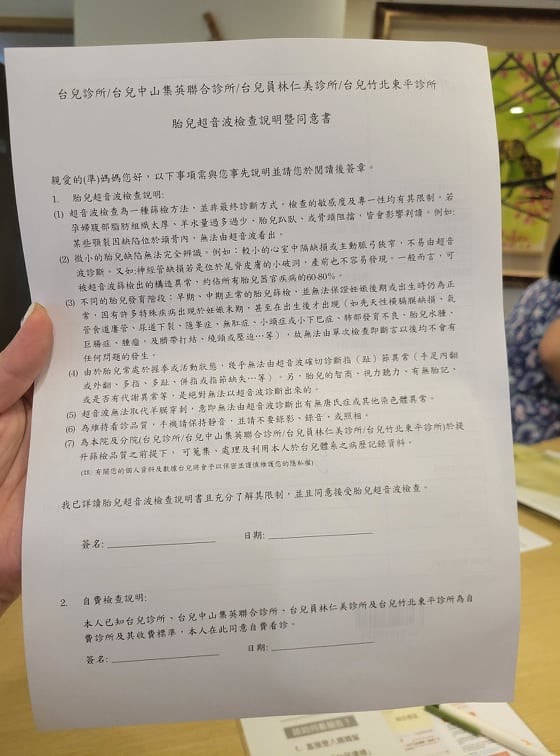

開始做檢查之前

也是會填寫一些資料

基本流程的概念